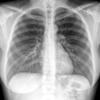

Normal PA Female

Date: 12/06/2014

Views: 6215